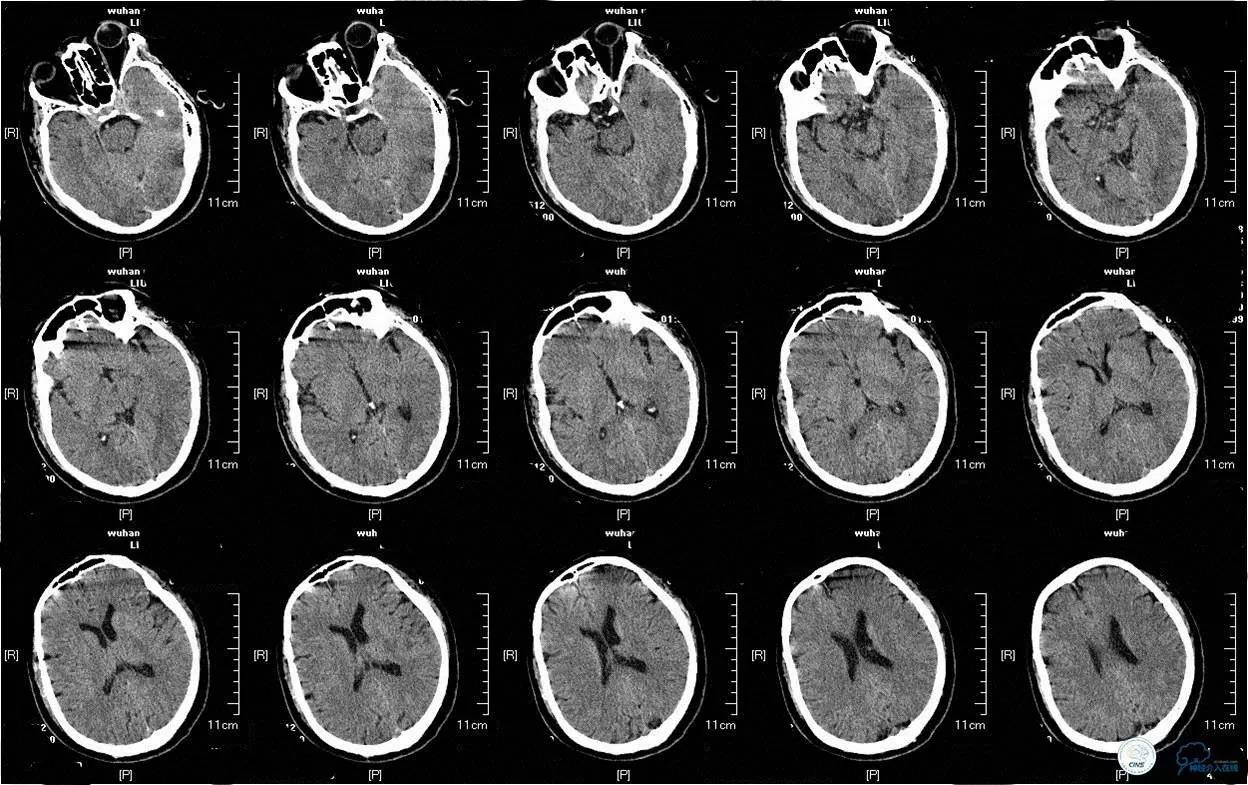

▼ 急诊CT显示无出血及新发的低密度病灶。